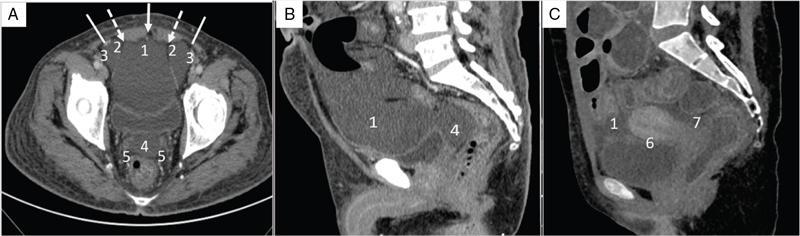

Shivsamb Jalkote, Slesha Bhalja, Disha Lokhandwala, Mansi Jantre, Karthik Ganesan Peritoneum is involved in a diverse group of primary as well as secondary pathologies ranging from the infective/inflammatory spectrum to malignancies. Peritoneal diseases are both common and potentially life threatening, and yet often get neglected in routine evaluation, due to the complex peritoneal anatomy and sometimes subtle imaging manifestations. The radiologist forms an integral part of the multidisciplinary team dealing with peritoneal pathologies and hence, having a lucid understanding of peritoneal anatomy, pathways of disease spread and different treatment options is paramount for an accurate radiological analysis. All three major serosal cavities (pleural, pericardial and peritoneal) of the body are derived from a single coelomic cavity, which is lined by a continuous mesothelium. At 2 weeks of gestational age, during the gastrulation stage, the embryo is a trilaminar disc, composed of the endoderm, mesoderm and ectoderm. During this stage, the development of the coelomic cavity commences as a consequence of morphological changes in the mesodermal cells leading to a coalition of the intercellular spaces. Peritoneum originates from mesoderm with its parietal layer developing from somatic mesoderm and visceral layer developing from splanchnic mesoderm. Initially, the peritoneum is an empty sac into which the growing gut tube protrudes (at 3 weeks of gestational age), resulting in the formation of the dorsal mesentery (formed by the fusion of two layers of the splanchnopleuric mesoderm) by which the gut tube is suspended lengthwise. The mesodermal cells opposed to the gut tube represent the future visceral peritoneum and those lining the body wall and the septum transversum form the future parietal peritoneum. Analogously, the ventral mesentery originates from the mesoderm of the septum transversum with the closure of the anterior abdominal wall, and, is short and not as extensive as the dorsal mesentery. The two mesenteries are aligned in the sagittal plane, subdividing the primitive peritoneum into right and left cavities, which are continuous anteriorly below the inferior edge of the ventral mesentery. With the development of various abdominal organs as buds from the gut tube, the capacity of the abdominal cavity diminishes, pushing the midgut loop into the umbilical cord. This physiologic herniation of the midgut takes place at the 6th week of gestation. Simultaneously, as the peritoneum drapes over the developing organs, there is compartmentalization of the cavity and a pattern of folds develops that eventually form the peritoneal ligaments. The majority of these ligaments arise from the ventral or dorsal mesentery. As the hepatic bud develops within the ventral mesentery, derivatives of the ventral mesentery can be divided based on their relation to the liver. The gastrohepatic ligament (lesser omentum) develops dorsally and the falciform, coronary, and triangular ligaments develop ventral to the liver. Conversely, the dorsal mesentery spans between the gut tube and the posterior abdominal wall, and the spleen and pancreatic tail develop within it. In congruence, it forms the gastrophrenic, gastrosplenic and splenorenal ligaments and peritoneal folds of the small and large intestines. As stated earlier, the dorsal mesentery has a relatively larger caudad extension and since the spleen develops in its upper portion, the rapidly growing mesentery beyond the spleen forms the greater omentum. Finally, the differential growth of the greater curvature of the stomach and the right hepatic lobe results in rotation of the abdominal organs and their mesentery, and the cephalad portion of the peritoneal cavity is divided into a larger ventral cavity, called the greater sac, which caudally communicates with the common peritoneal cavity, and a smaller dorsal cavity called the lesser sac. The key aspects of peritoneal development are summarized in Flowchart 8.6.1 and Fig. 8.6.1. Laparoscopy remains the gold standard in the assessment of peritoneal disease, however, it is an invasive technique, and has certain diagnostic limitations including the inability to assess parenchymal diseases, extraperitoneal diseases, and also has limited utility in the presence of adhesions. Hence laparoscopy is not recommended as the first-line modality and has been replaced by cross-sectional imaging in routine clinical practice. The role of imaging is primarily to assess disease burden in terms of volume and extent and to identify surgically nontreatable disease, which reduces open and shut laparotomies. Peritoneal metastatic disease burden is assessed using peritoneal carcinomatosis index (PCI) both surgically as well as using cross-sectional imaging, details of which will be discussed subsequently. CT, MRI and PET/CT are all commonly used imaging modalities, however, there is no singular universally accepted reference imaging standard for the peritoneal disease. In a recent meta-analysis evaluating the diagnostic performance of imaging in the detection of peritoneal metastasis (PM), authors concluded that MRI (DWI) and PET/CT show comparable diagnostic performance in gastrointestinal and ovarian cancer malignancies however the widespread availability of MRI makes it the more likely imaging modality of choice in the future. The results of this study are summarized in Table 8.6.1. Conventional imaging including radiography and barium studies have a poor diagnostic yield in evaluating peritoneal pathologies. Abdominal radiographs are usually restricted for identifying pneumoperitoneum and bowel obstruction in the setting of acute abdominal pain. Diffuse increase in radio-opacity of the abdomen, poor definition of soft tissue shadows (psoas, liver and spleen), bulging flanks along with medial displacement of small bowel loops from the properitoneal fat stripe are indirect markers of large ascites which can prompt further evaluation with ultrasonography. Indirect features of peritoneal disease on barium studies include mass effect and displacement of adjoining bowel loop, narrowing of bowel loop with bowel dilatation along with nodularity, spiculation, or tethering of adjacent mucosal folds or haustra with sacculation of the uninvolved contralateral border. Barium studies have fallen out of favour in routine radiological practice owing to the widespread use of cross-sectional imaging. Ultrasonography (US) is a readily available and relatively inexpensive imaging tool. Traditionally its role in the evaluation of peritoneal pathologies is limited as US beam gets strongly reflected at the interface of air and visceral structures which leads to obscuration of underlying structures. US remains the primary imaging modality in the evaluation of an acute abdomen and is useful in detecting of ascites, focal lesions and any focal abnormality at the site of tenderness. US has the unparalleled advantage of providing real-time assistance in performing imaging-guided procedures such as paracentesis and peritoneal biopsies. US can be used in characterization of focal lesions (as solid, solid-cystic and cystic) and assessment of internal vascularity using colour Doppler. Transvaginal US provides a good overview of pathologies involving pouch of Douglas besides the uterus and adnexa. Experienced and skilled sonologists can detect omental thickening, peritoneal nodules and small surface deposits using high-frequency transducer (Fig. 8.6.2). Endoscopic US allows assessment of diseases involving peritoneal ligaments besides assistance in a guided biopsy. The reported sensitivity, specificity and accuracy of EUS-FNA versus CT/MRI in detecting PM was 91% versus 28%, 100% versus 85% and 94% versus 47%, respectively. CT is the most commonly employed imaging modality in the evaluation of peritoneal pathologies due to its widespread availability, fast acquisition and high spatial resolution. Current generation multidetector CT scanners (64 slices and above) offer very thin collimation, leading to the acquisition of near isotropic volumetric data which allow reformations in coronal and sagittal images without any added imaging time. It is the modality of choice for preoperative staging in most primary abdominal and pelvic malignancies (e.g. stomach, appendix, ovary) owing to its ability to detect local and regional infiltration, nodal involvement and distant metastases. CT is also used to evaluate PCI and detect disease in critical and occult locations, thus significantly altering further management strategies. CT is the most common imaging modality used in postoperative surveillance and evaluation of postoperative recurrence. CT protocol includes administration of both enteric contrasts (oral and rectal) and intravenous contrast (Table 8.6.2). Optimal bowel distension is key as collapsed loops can mimic disease and also mask the serosal and endoluminal disease. Often, a CT scan of the chest is performed as an adjunct to rule out pleuroperitoneal/transdiaphragmatic dissemination. Helical (≥64 slice scanner) Dual energy scanner if available As thin as possible (≤1 mm) Same as section thickness without gap From xiphisternum to pubic symphysis Chest included if suspicion of thoracic involvement 1 L of positive oral contrast over duration of 60 minutes and 500 mL of positive rectal contrast on table before administration of IV contrast 1.5–2 mL/kg of nonionic contrast with high iodine concentration (≥ 300) at rate of 3–5 mL/sec Unenhanced imaging not recommended. Monophasic acquisition at 60 seconds usually sufficient in majority cases Arterial phase at 20 seconds acquired for arterial assessment Delayed phase in cases of ureteric obstruction, slow bowel transit and suspected leak. Axial 1 mm thickness, multiplanar reformats in coronal and sagittal planes at 1 mm MIP or 3D volumetric sections for vascular assessment There is a wide range of reported diagnostic accuracy (sensitivity ranging from 25% to 100%, specificity ranging from 78% to 100%) of CT in the assessment of PM depending on the expertise of the reader and scanner type. In general, key factors affecting CT sensitivity include the size of lesion, the region of affection and presence of ascites. 64 slice scanners with multiplanar reformations allow 100% sensitivity and positive predictive value in detecting lesions measuring >5 cm, which partly diminishes for lesions between 0.5 cm and 5 cm in size with sensitivity and positive predictive being 83% and 93%, respectively. It receives the most criticism in the evaluation of lesions < 0.5 cm with significantly low sensitivity and positive predictive value (43% and 76%, respectively). There is also a great degree of variation in sensitivity based on the anatomical location of the disease. In a study by Koh et al., the detection rates ranged from 8% to 67%, depending on the region involved; only the epigastrium exceeded 60%, with the small-bowel disease being the most poorly visualized (8%–14%). The sensitivity for tumour detection in epigastrium, greater omentum and under surfaces of the diaphragms was 60%–90%, while it was 50%–70% in the retroperitoneum and pelvis, and small bowel-mesentery involvement was detected in merely 20%–50% of cases. These are noteworthy findings, as small-bowel involvement has major implications on outcome and is one of the limiting factors for complete cytoreduction. Poor soft tissue resolution of CT doesn’t allow accurate differentiation between mucinous deposits from ascites. Administration of positive enteric contrast can mask calcified serosal deposits. DECT uses two separate x-ray energy spectra and allows characterization of tissues based on their differences in attenuation properties at different energies. Though the role of DECT in the assessment of abdominal pathologies is increasingly reported in the literature, there are very limited data available on its application in assessment of peritoneal pathologies. The combination of iodine overlay with conventional imaging has shown a better specificity in differentiating PM from benign peritoneal entities, and hence can be particularly useful in the postoperative setting. MR imaging offers excellent soft tissue resolution, multiplanar capabilities and avoids exposure to ionizing radiation, making it an attractive tool for evaluation of peritoneal diseases. MRI is better suited and can be problem solving in visualization of smaller lesions (<1 cm) and assessment of relatively concealed areas such as subphrenic, mesenteric and bowel serosa. Unenhanced T1- and T2-weighted images can show larger peritoneal deposits and masses but are relatively insensitive for the depiction of smaller lesions. The combination of diffusion-weighted imaging (DWI) and delayed gadolinium-enhanced MR imaging is considered the most accurate technique for detecting peritoneal tumours (Fig. 8.6.3). MRI protocol for assessment of peritoneum has been detailed in Table 8.6.3. In a study by Low RN et al., MRI PCI correctly categorized tumour volume in 91% of patients compared to surgical PCI, as opposed to 50% with CT. In addition, MRI demonstrated per site sensitivity of 95%, specificity of 70% and accuracy of 88%, while CT showed a corresponding per site sensitivity of 55%, specificity of 86% and accuracy of 63%. MRI PCI has also shown to have better prediction of intraoperative burden of disease for invasive appendiceal and peritoneal mesothelioma histologies as compared to CT-PCI. *This general imaging protocol is based on 3 T MRI Siemens system, covers both abdomen and pelvis. Protocol is modified depending on primary disease and type of scanner. Low RN. Preoperative and surveillance MR imaging of patients undergoing cytoreductive surgery and heated intraperitoneal chemotherapy. Journal of gastrointestinal oncology. 2016 Feb;7(1):58. The higher cellularity of majority of peritoneal nodules results in restriction of water movement and corresponding high signal intensity on DW images. On the higher b-value images, bowel contents are suppressed and the serosal and peritoneal tumours become hyperintense. DWI is also useful to demonstrate associated lymphadenopathy, hepatic and osseous metastases. In a study by Zhang et al., in PC of colorectal carcinoma, DWI demonstrated sensitivity of 69.4%, 91.3% and 100% for lesions measuring <0.5 cm, 0.5–5.0 cm and >5 cm, respectively. The overall sensitivity, specificity and accuracy of DWI for the detection of peritoneal tumours were 80.3%, 84.5% and 82.1%, respectively. DWI/MRI is also superior in demonstrating lesions involving small bowel wall, with an accuracy of 92%–95% versus 48% for CT. Reported negative predictive value of DWI for small bowel serosal metastases is 100%. Whole-body DWI/MRI was highly accurate for the prediction of inoperability (PPV 100%, NPV 90.3%) and was capable of detecting metastases both inside and outside the abdominal cavity. Peritoneal tumours enhance slowly and are best depicted on the final set of images obtained about 5 minutes following gadolinium administration. The increased conspicuity of these enhancing peritoneal tumours improved detection of small tumours that are often missed on CT scans. For this reason, perfect breathhold is essential while obtaining the final set of images and if images are acquired later, contrast that has diffused into the ascitic fluid can obscure smaller lesions. The high-contrast conspicuity of fat-suppressed and delayed gadolinium-enhanced MRI makes it the imaging modality of choice in depicting subcentimetre deposits (including those measuring <5 mm), and also deposits in anatomically concealed sites (e.g., subphrenic, mesenteric and bowel serosa). Gadolinium-enhanced MRI has higher sensitivity in detecting peritoneal lesions <1 cm which is about 85%–90% compared to 22%–33% for CT. Despite the clear superiority of MRI over CT, the major detractors against MRI are the long exam times and the higher expense burden. Longer acquisition times can lead to motion artefacts related to respiration and bowel peristalsis compromising detection of smaller lesions. MRI is contraindicated in patients with pacemakers, cochlear implants and claustrophobic patients with some exceptions. DW-MRI is less sensitive in special histological subtypes such as signet ring cell and mucinous adenocarcinoma due to their limited restricted diffusion. The combined use of FDG-PET with anatomical CT imaging, provides the added benefit of qualitative and semiquantitative metabolic analysis (Fig. 8.6.4). PET/CT has an established role in staging of most of the primary tumours of the chest, abdomen and pelvis. It is also helpful in assessing malignant ascites or PM of an unknown primary. In disseminated malignancies, it can localize the optimal site for biopsy depending upon metabolic activity of the lesion. PET/CT should be used selectively in preoperative assessment of patients with large tumour volumes and poor prognostic histologies being considered for CRS and HIPEC to rule out extra abdominal metastases. It can also detect extraabdominal metastases, including mediastinal and supraclavicular nodes, and other organ sites, such as bone and brain. It can also detect nodal involvement in normal-sized lymph nodes seen on conventional cross-sectional imaging. PET/CT also plays a role in disease surveillance and assessment of response to neoadjuvant chemotherapy. This is particularly relevant in malignancies where anatomical changes are so small that measurement of size change alone becomes unreliable and also in differentiating between residual/recurrent disease and postoperative changes after CRS and HIPEC. Besides oncological indications, PET/CT is also helpful in assessment of benign and inflammatory diseases to evaluate disease extent and also localize the site for biopsy. In cases of pyrexia of unknown origin, PET/CT has often been employed to demonstrate unsuspected peritoneal disease. Utility of PET/CT in peritoneal disease assessment is limited in developing counties due to its higher cost burden and lower accessibility. Certain histological subtypes such as mucinous and signet ring cell carcinomas show low FDG uptake making PET/CT less sensitive. Low metabolic uptake in these subtypes is thought to be due to low tumour cell density, higher content of metabolically inert mucin and lack of expression of glucose transporter Glut-1. This is more relevant in context of colorectal malignancy where mucinous carcinoma and signet ring cell carcinoma more frequently metastasize to the peritoneum compared to adenocarcinoma (48%, 51% and 20%, respectively). PET/CT is prone to artefacts caused by misregistration between the CT and PET images which can lead to inaccurate assessment of certain regions such as dome of diaphragm and structures adjoining the urinary bladder, making the detection of pelvic implants difficult due to partial volume effects. Implants against the small bowel and mesentery may be obscured by the physiological metabolic activity of bowel. Pretreatment PET/CT demonstrates a higher accuracy than CT for nodal and metastasis staging but has limited sensitivity to detect PM, especially when there is small-volume disease as only 13.6% of the nodules less than 0.5 cm were correctly identified by PET/CT. Table 8.6.4 summarizes role of different imaging modalities for assessment of peritoneal diseases. Peritoneum is the largest serosal membrane in human body with surface area of about 2.2 m2. It is composed of parietal and visceral layers which are continuous with each other, with parietal peritoneum lining the coelomic cavity and visceral peritoneum lining the visceral organ (Fig. 8.6.5). The peritoneum essentially minimizes friction, resists infection and stores fat, allows free movement of the abdominal viscera which gets restricted in presence of adhesions. Peritoneum acts as first line of defence in controlling disease spread, and, it exudes fluid and cells in response to injury or infection (peritonitis), to wall off or localize infection. In natural states, intraperitoneal spread of infection is limited by lymphoid aggregates and stomata on both the peritoneal layers. Omentum is commonly known as policeman of abdomen as it migrates to the site of infection and isolates affected area from healthy tissues. Iatrogenic violation of peritoneum following surgery can lead to recurrence along the operative incision scar sites and along the vaginal cuff following hysterectomy in pelvic malignancies. The parietal peritoneum is supplied by nerves (e.g. phrenic and thoracoabdominal) to the adjacent body wall, and is predominantly very sensitive to pain, which explains the typical referred shoulder pain from upper abdominal pathologies such as gall stones and pancreatitis. The visceral peritoneum is insensitive to pain and responds mainly to stretching. These two layers encompass a potential space, called the peritoneal cavity which contains approximately 50–75 mL of clear serous fluid. Peritoneal cavity is a closed space in males while in females it communicates with extraperitoneal pelvis through ostia of fallopian tubes allowing transport of ovum. This communication serves as natural route for ascending spread of sexual transmitted disease from genital organs into peritoneal cavity leading to pelvic inflammatory disease and uncommonly perihepatitis (Fitz–Hugh–Curtis syndrome). The invaginations of the peritoneum result into formation of three different types of structures namely ligaments, omentum and mesentery (Figs. 8.6.6–8.6.9) which serve as bridges that permit blood, lymph vessels and nerves to reach the viscera. Ligaments are double folds of peritoneum that connect one organ to another organ or to the abdominal wall and are named usually after the respective viscera. The liver, for example, is connected to the diaphragm by the falciform ligament, coronary ligament and right and left triangular ligaments. Mesenteries are double folds of peritoneum that suspend intestine to the posterior abdominal wall (retroperitoneum) such as the small bowel mesentery, transverse and sigmoid mesocolon. Omentum are double folds of peritoneum that extends from the stomach to other organs and include the greater and lesser omentum. Table 8.6.5 summarizes the peritoneal ligaments in abdomen and pelvis. In medical school days, the anatomy textbooks traditionally divided abdomen and pelvis into tricompartmental model comprising of peritoneal cavity, retroperitoneum and extraperitoneal spaces. This model is good for basic understanding of anatomy and confinement of certain disease processes but fails to explain spread of diseases from retroperitoneum to peritoneum besides spread of some disease processes within peritoneal cavity itself. Considering these shortcomings of conventional description of anatomy, the unifying concept of subperitoneal space has evolved in literature and is getting accepted increasingly. As per this concept, abdomen and pelvis are divided in two spaces peritoneal cavity and subperitoneal space which are separated from each other by peritoneum. Subperitoneal space (Fig. 8.6.10) is large anatomically continuous potential space which connects peritoneal cavity with retroperitoneum. It constitutes the subserosal areolar tissue and fat tissue lining the inner surfaces of the peritoneum and the abdominopelvic musculature. The omentum, ligament and mesentery are the interconnecting peritoneal folds building the subperitoneal space. All the abdominal and pelvic organs along with their vascular, lymphatic and nervous supplies are situated within subperitoneal space. With this concept, we want to correct the common misconception of intraperitoneal organs as in strict terminology there is no organ within the peritoneal cavity itself. It is imperial to understand differences between peritoneal and subperitoneal spaces as these are mutually exclusive spaces having distinct patterns of disease spread which we will discuss in subsequent sections. In resting state, peritoneal cavity is collapsed and thus not visible on routine imaging. Peritoneal cavity usually gets distended due to disease processes composed of fluid, air or masses. The peritoneal cavity is divided into two parts: the greater sac and the lesser sac which communicate with each other via an epiploic foramen (of Winslow). The greater sac forms main peritoneal cavity and extends from the diaphragm down into the pelvis. The lesser sac is small diverticulum and lies between stomach and pancreas. For better understanding, abdominal peritoneal cavity is divided into supra- and inframesocolic compartments, communicating with pelvic peritoneal cavity which is further divided by other peritoneal folds and reflection (Flowchart 8.6.2, Figs. 8.6.10 and 8.6.11). Supramesocolic compartment (Fig. 8.6.12) is situated between the diaphragm and transverse mesocolon. It is arbitrarily divided into right and left supramesocolic peritoneal spaces, which can be further subdivided into a number of subspaces by upper abdominal organs and peritoneal ligaments. Right supramesocolic space is divided into three subspaces: right subphrenic space, right subhepatic space and lesser sac. Right subphrenic space is partially separated from right subhepatic space by right triangular ligament. Right subphrenic space is situated between right hemidiaphragm and right lobe of liver (superior, anterior and right lateral surfaces). It is limited posteriorly by the coronary ligament and medially by the falciform ligament with the latter separating it from the left subphrenic space. Right subhepatic space is situated inferior to right lobe of liver and has anterior and posterior components. Anterior component is limited inferiorly by transverse mesocolon whereas the posterior component extends anterior to right anterior perirenal fascia. Posterior component of right subhepatic space is commonly known as hepatorenal pouch (of Morrison) and forms most dependent site in supine position, thus being a common site of fluid accumulation. The right subhepatic space freely communicates with right subphrenic space superiorly and right paracolic gutter inferiorly. Lesser sac (also known as omental bursa) is situated superior to the transverse mesocolon, anterior to pancreas and posterior to the lesser omentum, stomach and gastrocolic ligament. Lesser sac (Fig. 8.6.13) communicates with right subhepatic space (of greater sac) via epiploic foramen which is bounded by IVC posteriorly, free margin of hepatoduodenal ligament anteriorly, D1 (first part of duodenum) caudally and caudate lobe of liver rostrally. Division of lesser sac into smaller superior compartment (superior recess) and larger inferior compartment (inferior recess and splenic recess) is accomplished by prominent crescentic gastropancreatic fold (peritoneal fold overlying common hepatic and left gastric artery) which extends from neck of the pancreas to the upper part of lesser curvature of stomach. The superior recess is situated to the right of midline above pancreas and posterior to lesser omentum. It surrounds the medial aspect of the caudate lobe and superiorly into the fissure for the ligamentum venosum. Splenic recess extends to splenic hilum, and is limited by gastrohepatic ligament (anterior), gastrosplenic ligament (lateral) and splenopancreatic ligament (posterior). Inferior recess is located to left of midline, separates stomach from the pancreas and transverse mesocolon. In few cases, an infrapancreatic part can be seen due to persistence of inferior recess within the greater omentum or due to downward bowing of transverse mesocolon. Left supramesocolic space is wider than right supramesocolic space and is limited above by left hemidiaphragm and below by transverse mesocolon and phrenicocolic ligament. Left supramesocolic space (subphrenic part) is medially separated from right supramesocolic space by falciform ligament and inferiorly from left paracolic gutter by phrenicocolic ligament. It is divided into four communicating subspaces: anterior left subphrenic space, posterior left subphrenic space, anterior left perihepatic space and posterior left perihepatic space. All these spaces communicate with each other. The definitions of the boundaries of these spaces vary in literature. Anterior left subphrenic space is situated between gastric fundus and left hemidiaphragm. Posterior left subphrenic space (also known as perisplenic space) surrounds spleen. Anterior left perihepatic space is situated between anterosuperior aspect of left lobe of liver and left hemidiaphragm. Posterior left perihepatic space (also known as gastrohepatic recess) is situated between inferior aspect of left lobe of liver and lesser omentum. Inframesocolic compartment (Fig. 8.6.14) extends below transverse mesocolon to the level of pelvic brim and is divided into large central part and smaller paracolic part (lateral recesses). Central portion of inframesocolic compartment is unequally divided by obliquely oriented small bowel mesentery leading to formation of smaller right inframesocolic compartment and larger left inframesocolic compartment. Right inframesocolic space terminates at the ileocaecal junction and does not communicate with pelvis. Left inframesocolic space is in communication with pelvic peritoneal spaces except at the sigmoid mesocolon attachment which offers partial barrier. Peritoneal recesses on the posterior abdominal wall lateral to the ascending and descending colon form right and left paracolic gutters respectively. Both paracolic gutters communicate freely with pelvic peritoneal spaces. Right paracolic gutter is deeper than left gutter and is in free communication with right supramesocolic space. Left paracolic gutter is partially limited from left supramesocolic space due to presence phrenicocolic ligament. Pelvis constitutes about one-third of the total volume of the peritoneal cavity and is most dependent part in both supine and erect positions. Inferiorly peritoneum drapes over fundus of urinary bladder, anterior and posterior surface of uterus and upper posterior vagina in females and anterolateral surface of the upper rectum leading to formation of different peritoneal spaces. The urinary bladder subdivides pelvis into anterior and posterior paravesical spaces. The anterior paravesical space is further compartmentalized by remnant of the urachus (median umbilical ligament), the obliterated umbilical arteries (medial umbilical ligament), and the lateral umbilical ligaments (inferior epigastric vessels) into five fossae: the right and left lateral and medial inguinal fossae and the supravesical fossa. The supravesical space is seen in midline with medial and lateral inguinal fossae placed on either side. The supravesical space lies above urinary bladder between the two medial umbilical folds, is usually occupied by small bowel loops and fundus of distended urinary bladder. Just lateral to the supravesical space is the medial inguinal fossa, located between the medial and lateral umbilical folds. The femoral ring is located inferolaterally and hence ascitic fluid in the medial inguinal fossa can extend into the femoral canal. Finally, the lateral inguinal fossa is located between the lateral umbilical fold and parietal peritoneum (which reflects over the vas deferens or round ligament). It usually contains the cecum or ileum on the right and sigmoid colon on the left. Extension of ascitic fluid into the inguinal canal can occur through the deep inguinal ring, located anteromedial to the lateral inguinal fossa. The posterior paravesical space is a larger recess situated between the urinary bladder and rectum. In women, uterus further divides it into smaller vesicouterine and larger rectouterine spaces. The vesicouterine space is located between the urinary bladder and uterus and is formed as the peritoneum drapes the uterine body and fundus and then runs over the urinary bladder (along its posterosuperior surface). It is continuous with the supravesical space anteriorly and its depth varies with the degree of urinary bladder distension. The rectouterine pouch (of Douglas) is delimited anteriorly by the uterus and broad ligaments and posteriorly by the rectum. Lateral to this cul-de-sac on either side are the uterosacral ligaments that run from the sacrum to the uterine cervix that separate the rectouterine pouch from the laterally located ovarian fossae. In men, the rectovesical pouch is formed as the peritoneum runs from the rectum to the posterior surface of the bladder. Posteriorly, the peritoneal reflection from the upper rectum runs to the pelvic sidewalls, forming right and left pararectal fossae, which vary in size with the degree of rectal distension. Analogous to the uterosacral ligaments in women, the rectovesical space is restricted by sacrogenital folds on either side, which extend from the urinary bladder to the sacrum. The rectovesical space and rectouterine space (pouch of Douglas) form most dependent areas in both in supine and standing positions in males and females, respectively (both in supine and standing positions). The key aspects of pelvic peritoneal spaces are summarized in Flowchart 8.6.3, Figs. 8.6.15 and 8.6.16. Peritoneal recesses represent small pockets or fossae in the peritoneal cavity bounded by folds of peritoneum and possibly represent developmental aberrations. Knowledge of these recesses is important as they can serve as pathways for internal hernias. Multiple peritoneal folds may surround fourth part of duodenum (D4) and duodenojejunal junction forming duodenal recess. Six major duodenal recesses include superior, inferior, paraduodenal, retroduodenal, duodenojejunal and mesentericoparietal recess. The superior duodenal recess is situated to the upper left side of fourth part of duodenum (D4) behind the superior duodenal fold at L2 level. Inferior mesenteric vein is situated behind lateral end of superior duodenal fold. Inferior duodenal recess is situated on left of D4 below DJ flexure and behind the inferior duodenal fold at L3 level. Inferior duodenal recess often exists in association with superior duodenal recess. Reported incidence of superior and inferior duodenal recesses is about 40%–50% and 70%–75%, respectively. Paraduodenal recess is seen on left side and slightly behind D4 bounded anteriorly by paraduodenal (falciform fold). Right free margin of paraduodenal fold contains the inferior mesenteric vein and an ascending branch of the left colic artery. This recess is seen in about 2%–3.8% cases and is site for left paraduodenal hernia. Retroduodenal recess as the name suggests situated behind the third and fourth parts of the duodenum and in front of abdominal aorta. Its orifice is bounded anteriorly by duodenoparietal fold. Retroduodenal space is largest among all the duodenal recesses and is seen in about 2.5% cases. Duodenojejunal recess is situated between the duodenojejunal flexure and root of transverse mesocolon, hence also known as mesocolic recess. Its boundaries include pancreas (superior), left renal vein (inferior) and left kidney (left). Its opening lies between two peritoneal folds, is directed inferiorly and to the right. Duodenojejunal recess is seen in about 20% cases and is almost never associated with other duodenal recesses. Mesentericoparietal recess is situated below third part of duodenum and behind the upper part of the mesentery. Its opening is bounded anteriorly by the fold of mesentery raised by the superior mesenteric artery. This recess is most rare among all with incidence of about 1%. It is the site for right paraduodenal hernia. The key aspects of duodenal recesses are summarized in Table 8.6.6 and Fig. 8.6.17. Peritoneal folds adjoining cecum result in formation of four main recesses: superior ileocaecal recess, inferior ileocaecal recess, retrocaecal recess and paracolic recess (Fig. 8.6.18). Surgically these recesses are important as they can be sites for internal herniation (except for paracolic sulci) or site of abscess formation in complicated appendicitis. Superior ileocaecal recess is bounded in front by the vascular fold of the cecum (containing anterior caecal vessels), behind by the ileal mesentery, below by the terminal ileum and on the right by the ileocaecal junction with its opening on left. Inferior ileocaecal recess is bounded in front by the ileocaecal fold (bloodless fold of Treves), above by the terminal ileum and its mesentery, to the right by the caecum, and behind by the upper part of the mesoappendix with its opening on left. Retrocaecal recess is bounded in front by posterior wall of cecum (and sometimes the proximal ascending colon), behind by the parietal peritoneum (posterior abdominal wall), and on either side by two caecal folds (parietocolic folds). Retrocaecal recess is largest among all the caecal recesses with its opening inferiorly and often contains appendix. Paracolic sulci represent variable one or more shallow lateral depressions in the peritoneum investing the cecum usually within the right paracolic gutter. This recess lies behind and inferior to the apex of inverted V-shaped root of sigmoid mesocolon with orifice opening inferiorly. Posteriorly, it is limited by parietal peritoneum of covering the left ureter at its iliac vessel crossing. This recess can be variable in size ranging from dimple to a small fossa in majority of the cases usually admitting little finger. It forms most common site of sigmoid mesocolon hernia. It can also be involved by peritoneal fluid and metastatic disease. Peritoneal and subperitoneal spaces are mutually exclusive spaces having distinct patterns of disease spread. Different pathways of the intraabdominal and extraabdominal disease spread are summarized in Table 8.6.7.

PET/CT